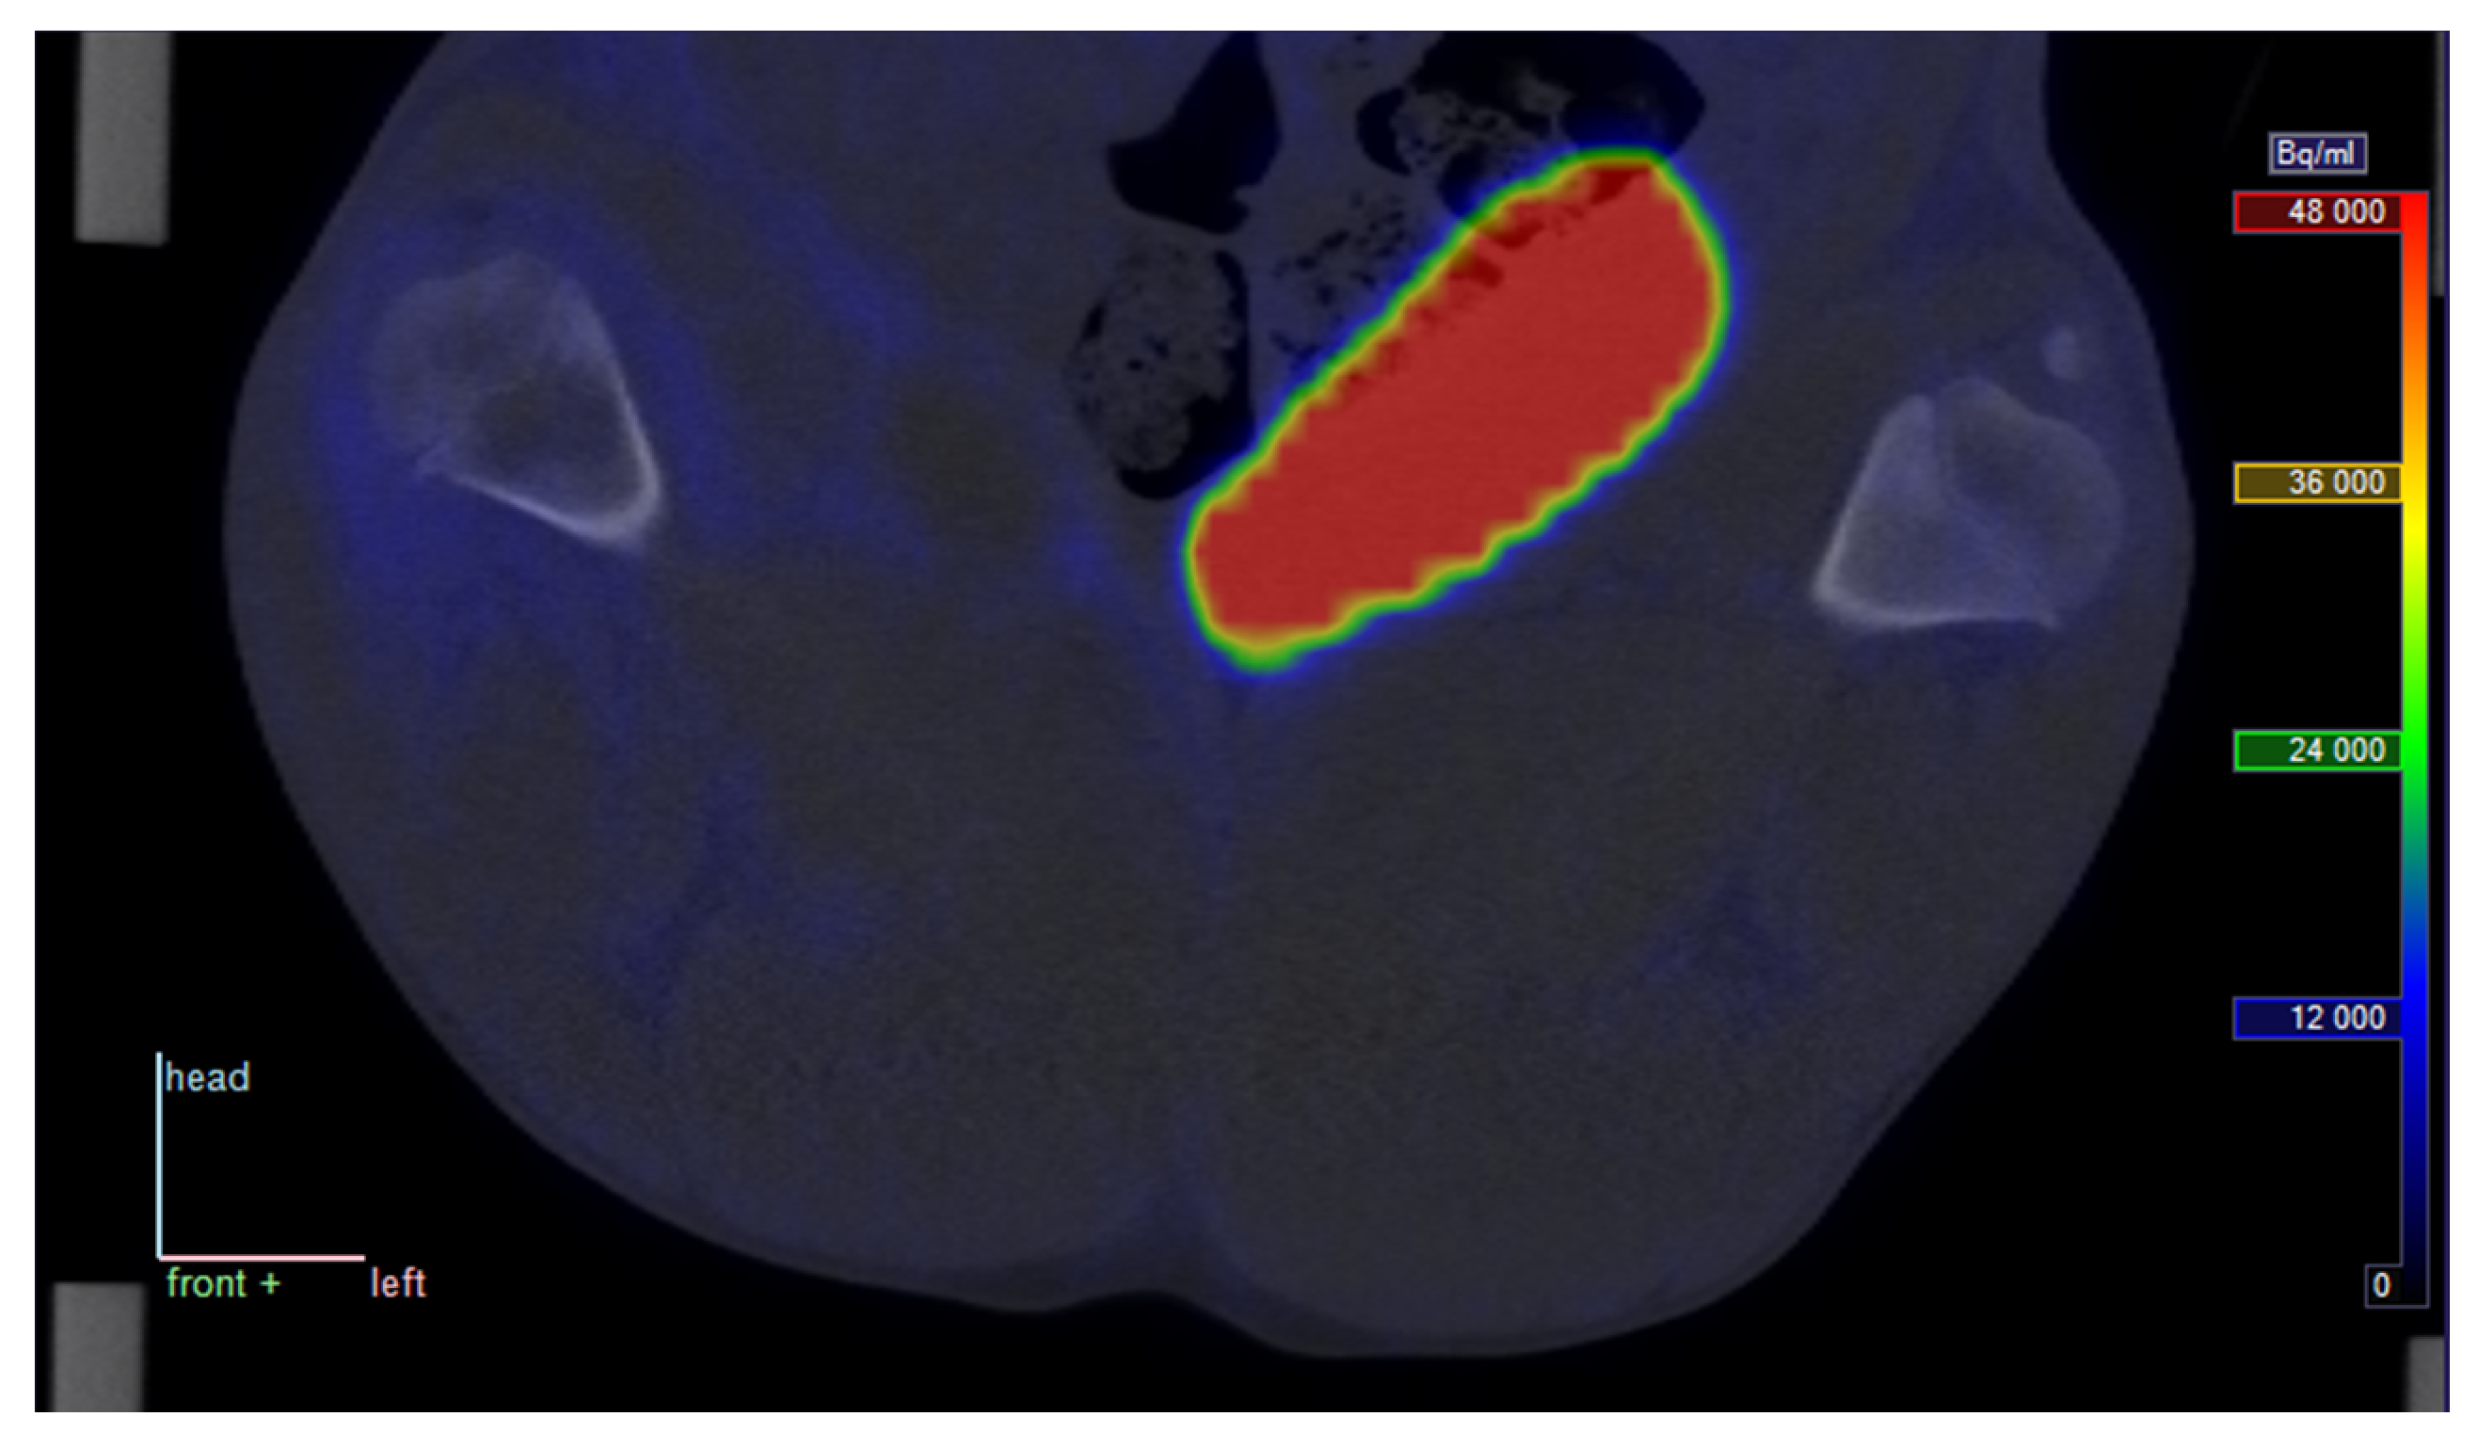

At late time points, the decay-corrected PET signal was markedly reduced in all tissues outside the bladder, indicating that uptake of the tracer is reversible rather than irreversible (see Figure 2).

Late PET/CT image from pig no. 25. Static scan with [68Ga]Ga-DOTA-Siglec-9 at approximately 70 min p.i.; position and colour scale correspond to those in Figure 1 (radioactivity is corrected for physical decay).